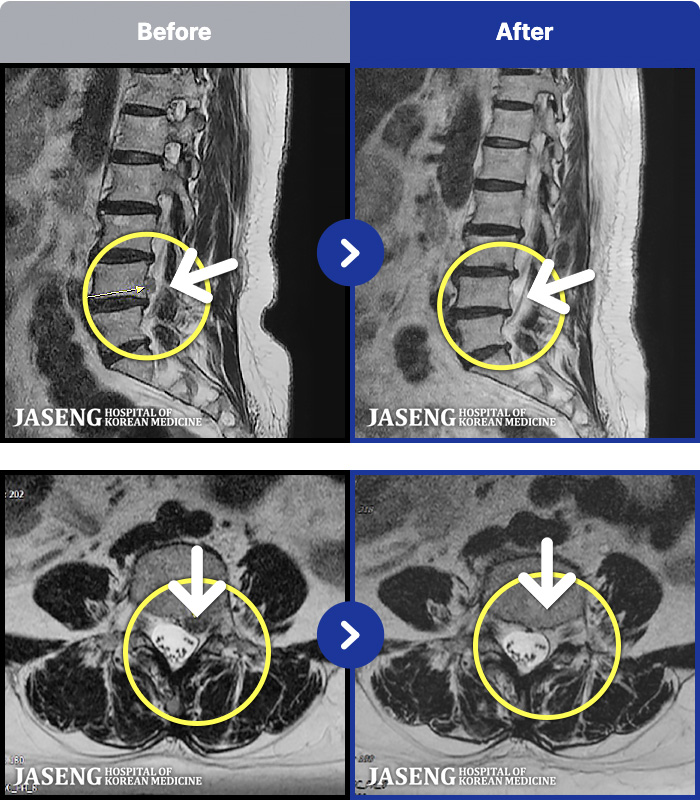

10년 전 허리디스크가 척추관협착증까지! 66세 고재임 어머님의 이야기